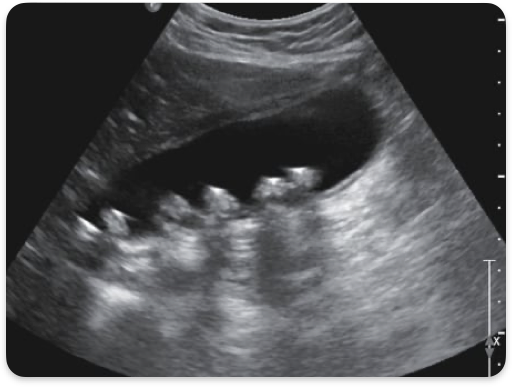

WES sign

GB completely filled w/ stones. Only anterior wall visualized

Cholelithiasis, gallstones